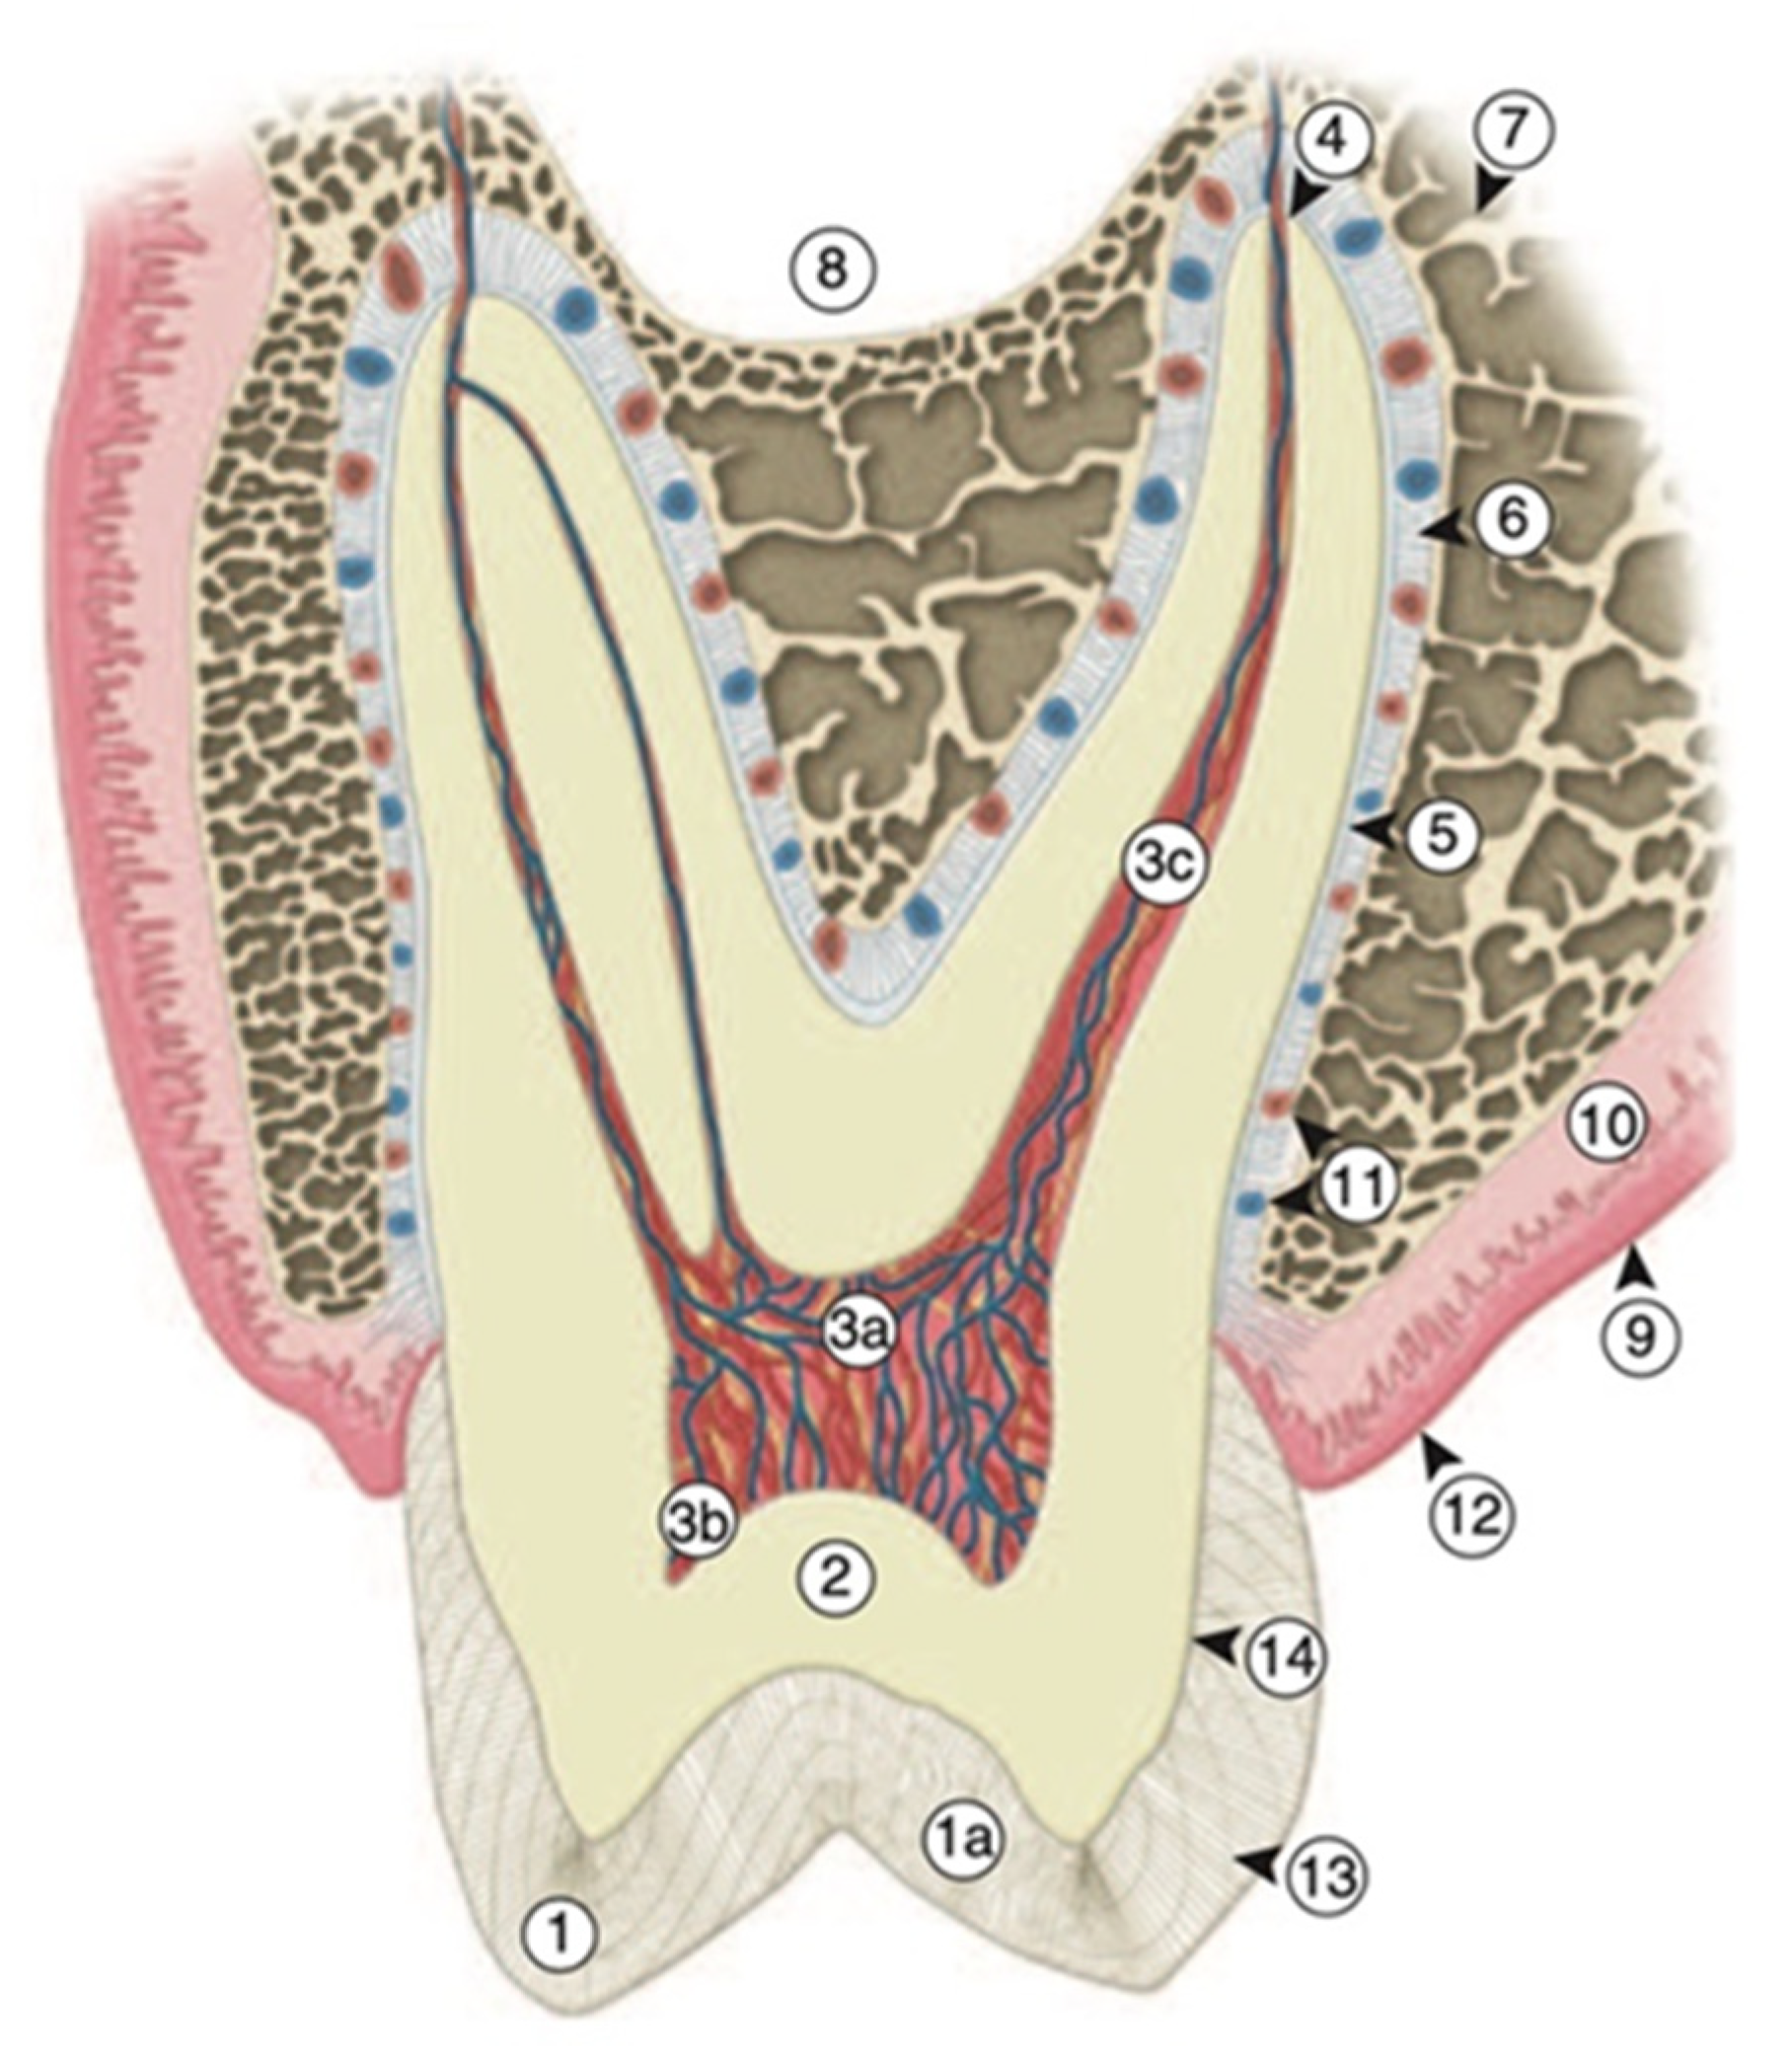

Biomimetics | Free Full-Text | Biomimetic Aspects of Restorative

The biomimetically driven restorative dental practice | Dental